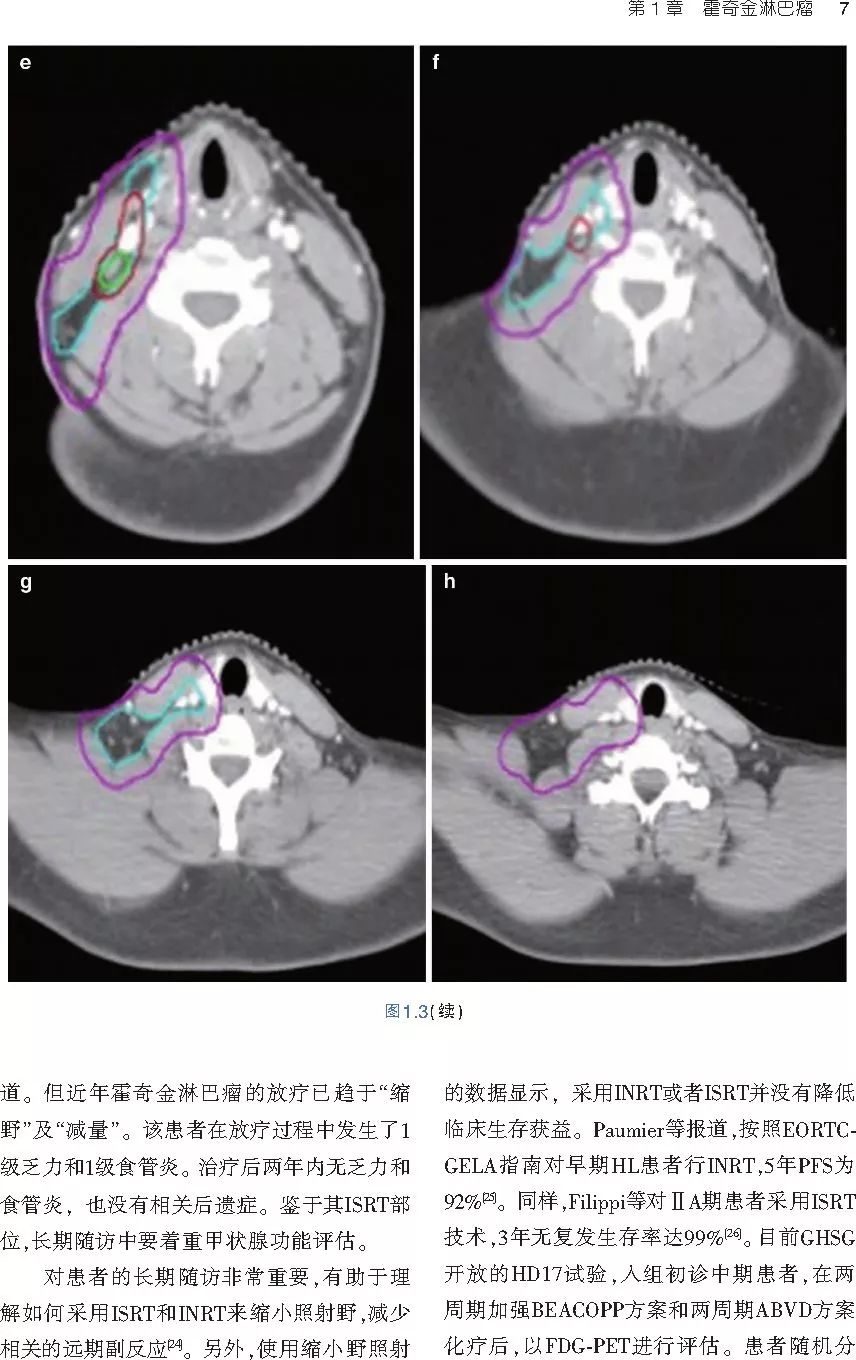

❤ 展开疾病诊断、病理描述及治疗方向的详细阐述,包含医学影像,图文并茂,深入浅出。

本书旨在帮助临床医生对常见血液系统恶性肿瘤疑难病例进行管理,包括霍奇金淋巴瘤、非霍奇金淋巴瘤和白血病患者,并通过多个病例进行阐述。案例讨论遵循标准格式,包括临床描述,其次是与诊断相关的病理描述和分期,然后详细讨论治疗选择。最后,确定治疗方案,并提供所使用的规划放疗技术/方式的图像。对放射肿瘤医生进行临床决策非常有帮助,对于血液病临床医生也有很好的指导作用。

近年来,放射治疗技术得到了迅速发展,调强放疗、图像引导放疗及其他新技术方法等,对恶性肿瘤治疗产生了巨大影响。现代放疗技术使精确定位、靶区勾画及给量成为可能,实现了肿瘤局控率和生活质量的双赢,对血液系统恶性肿瘤的临床治疗也产生了一定的影响。此书内容上不仅反映了血液系统恶性肿瘤综合治疗的进步,更是对其中放射治疗的新变化进行了系统、详细的阐述,这对当前血液系统恶性肿瘤放射治疗临床实践具有非常好的指导作用和参考价值。